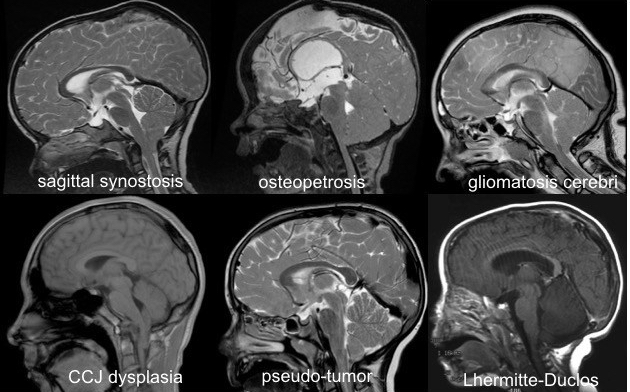

engagement tonsillaire chronique lié à différentes maladies du cerveau et de ses enveloppes. il s’agit ici de diagnostics différentiels de la malformation de Chiari.

devant un engagement tonsillaire chronique, il faudra donc rester vigilant et ne pas méconnaitre une pathologie plus complexe sous-jacente, sous peine de complications post-opératoires.